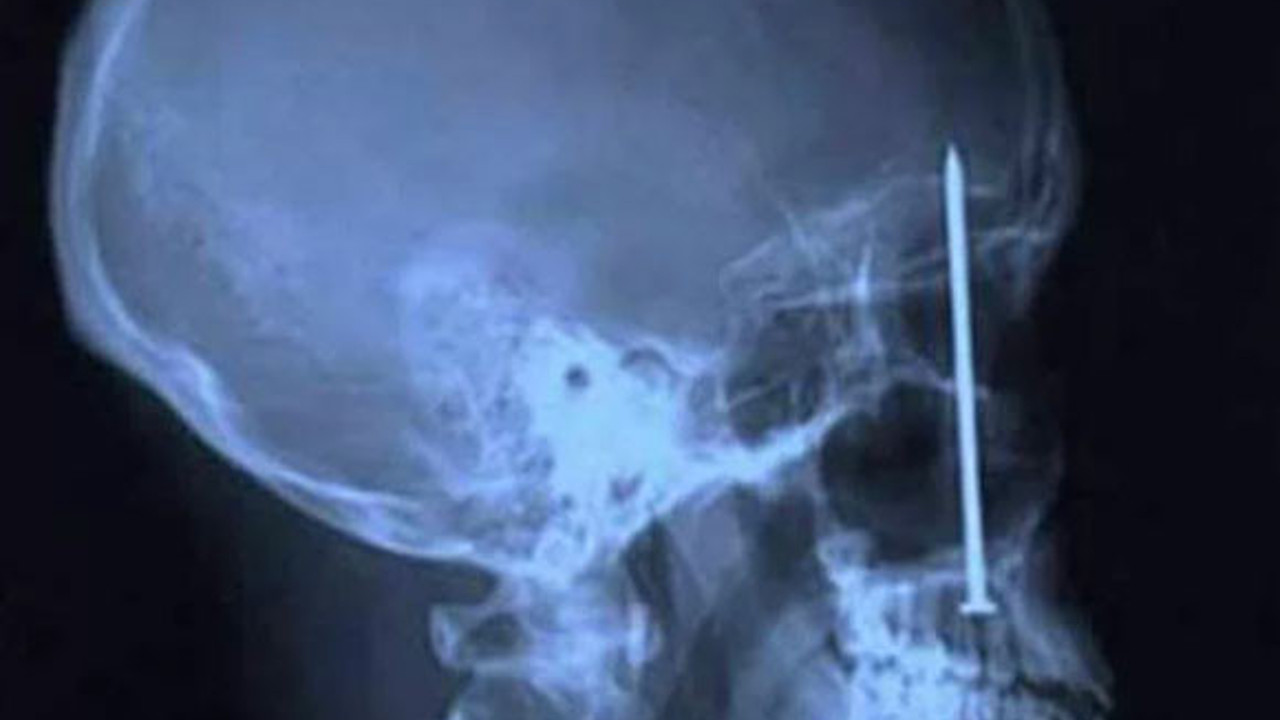

Diş Ağrısından Fazlası Bu Xray'in sahibinin o çiviyi oraya sokmasından daha ilginci, diş ağrısı sebebiyle dişçiye gittikten sonra orada bir çivinin olduğunu farketmesi.. Sürpriz evlenme teklifi Amerikalı bir adam, sevgilisine sürpriz yapmak için aldığı tektaş yüzüğü kızın milkshakeinin içine koyuyor.. Bu da sonucu Kafaya saplanan bıçak Silahlı soygun kurbanı bu arkadaş, tamamen iyileşmiş Ameliyatta makas unutma klasiği Kafada ok! Çin'de şakalaşırken arkadaşı tarafından kafasından okla vurulan çocuk. Neyse ki bu da iyileşmiş Kürdan niyetine makas Bu Çinli arkadaş da, dişinin arasına kaçan şeyi ufak makasla almaya çalışırken arkadaşları tarafndan güldürülünce yutuvermiş makası.. Kafasına Bıçak Giren Asker Tam gözünün üstünden kafasına yaklaşık 7 cm içeriye kadar bıçak girmiş olmasına rağmen bu asker de hasarsız bir şekilde hayata dönmüş.. Kafaya birşey girince ölünmüyor galiba !?! Makatta Ampul.. Hem de tersten :( Bu fantastiklik de Pakistan'dan.. Kolonda Cep Telefonu San Salvador'da bir hapishaneden.. İçeri cep telefonu sokmak için.. Kafaya Matkap Matkapla çalışırken merdivenden düşen inşaat işçisinin Xray görüntüsü.. O da hayatta! Yüzde Anahtar! 17 aylık çocuk Nicholas Holderman, bir şekilde annesinin anagtarlarını burnundan ve gözünden içeri sokmuş.. O da tamamen iyileşmiş! Dev böbrek taşı! İster inanın, ister inanmayın bu böbrek taşı Macaristan'daki bir hastanın içinde bulundu! Top Mermisi Evet top mermisi bir askerin makatında bulunuyor. İşin komiği ameliyat esnasında mermi yanlışlıkla patlamasın diye uzman bir ekip bulundurulmuş.. Çatal! İsrailli bir kadın yanlışlıkla yemek yerken hamam böceği yutuyor. Çıkartmak için de çatal kullanmaya çalışırken, onu da yutuyor.. Gerçekten insanların hiç farkında olmadan beyinlerine çivi saplayabilmesi çok acayip. Güney Kore'li bu adam da, başağrısı şikayetiyle doktora gelip beyninde bir çivi farkediyor İntihar bombacısının midesinde el bombası İntihar bombacılarının beynini yıkadıklarını biliyorduk da, bununkini fazla yıkamışlar galiba Sandalye Bacağı Shafique El-Fahkri isimli genç, barda kavga etmeme konusunda ders almış. 20 yaşındaki Liam Peart'ın attığı sandalye bu şekilde gözünden girip boğazına kadar gitmiş. Bu arkadaş da ölmemiş..